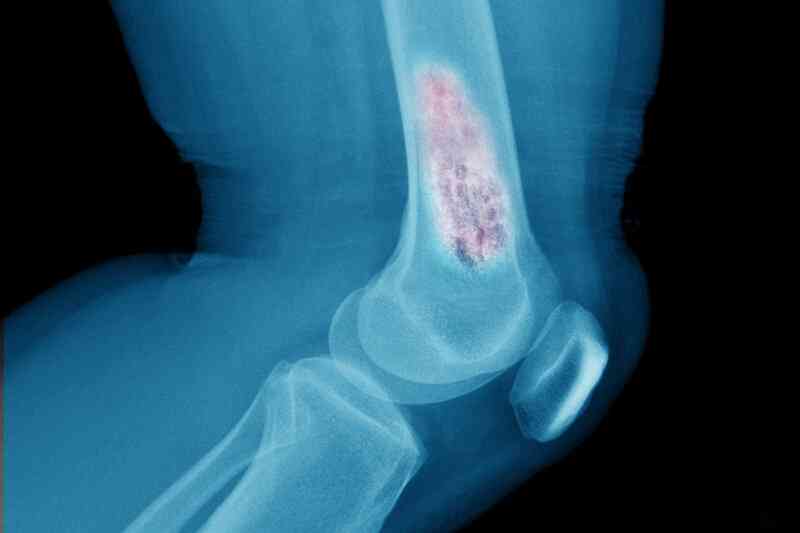

Xərçəngin sümüklərə yayılmasının əlamətləri

Yolğun bağırsaq xərçənginin sümüklərə yayılmasının üç əlaməti var.

Şişin sümüklərə yayılması xəstənin həyatı üçün ən böyük təhlükələrdən biridir.

Nadir hallarda yoğun bağırsaq xərçəngi sümüklərə yayıla bilər.

Medicina.az xəbər verir ki, onkoloqların fikrincə, xərçəngin sümüklərə yayılması hiperkalsemiyaya səbəb olur, qanda çoxlu kalsium toplanır.

Mütəxəssislər hesab edirlər ki, bu, yetkin xəstələrin 20%-də inkişaf edən yoğun bağırsaq xərçənginin ən çox yayılmış həyati təhlükəsi olan ağırlaşmasıdır.

Hiperkalsemiya adətən üç klassik simptomla özünü göstərir:

- Yorğunluq

- Özünü pis hiss etmək (ürəkbulanma)

- Susuzluq

Sümüklərə yayılmış şiş sümüklərə zərər verə və onları zəiflədə bilər, eləcə də şiddətli ağrıya səbəb ola bilər. Bu, sınıq riskini daha da artırır. Qeyd etmək vacibdir ki, hiperkalsemiya simptomlarının olması mütləq inkişaf etmiş bağırsaq xərçəngi demək deyil.

Lakin, digər gizli simptomlarla qarşılaşsanız, diqqətli olmalısınız:

- Mədə pozğunluğu

- Qusma